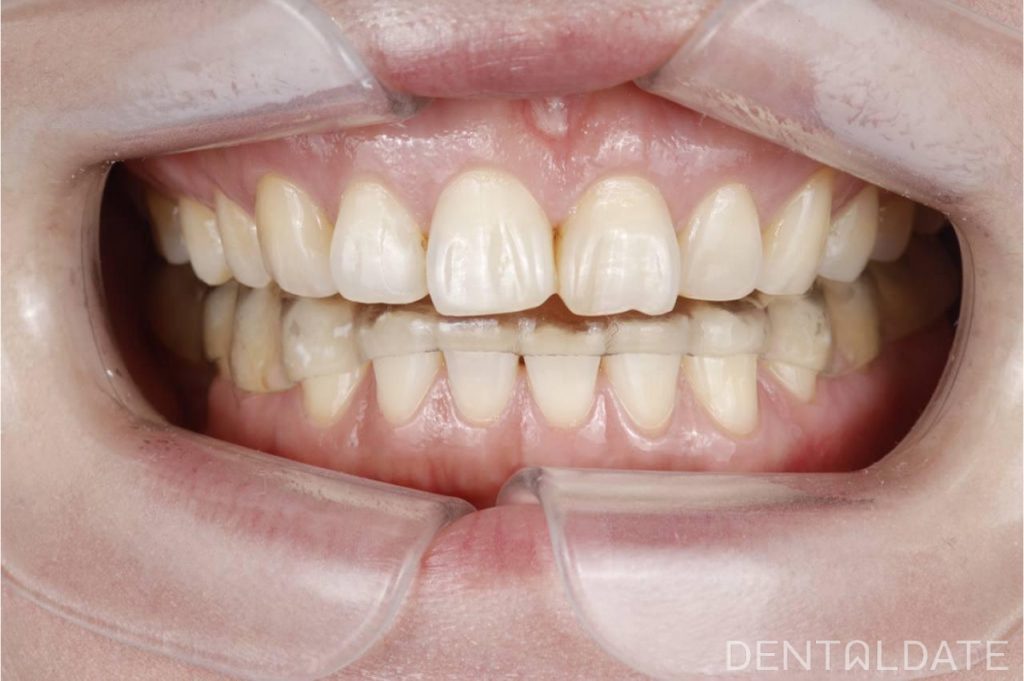

Complex treatment of TMJ arthrosis with orthodontic correction

In this clinical case, we want to demonstrate an approach focused on optimizing treatment timelines for temporomandibular joint (TMJ) osteoarthritis. The patient was diagnosed with TMJ osteoarthritis, confirmed by condylography and CT imaging.

To make the most of the adaptation phase, we simultaneously initiated orthodontic correction of the upper jaw. This approach allows us to significantly shorten the overall treatment time and achieve faster, more effective results.

This clinical case highlights the importance of a comprehensive approach and strategic treatment planning for TMJ disorders, enabling optimized timelines and improved therapy outcomes.